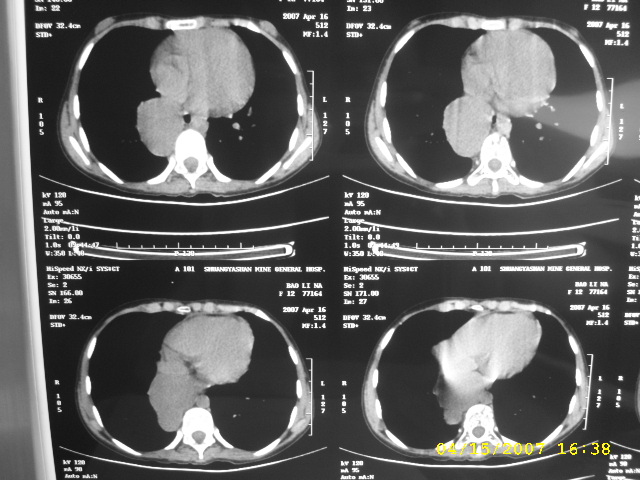

标题: PED0109:女,12,后纵隔占位十余年

女,12,后纵隔占位十余年。

女,12,后纵隔占位十余年,没什么特异性,考虑1纵隔囊肿2肺隔离症3神经源性肿瘤,建议增强